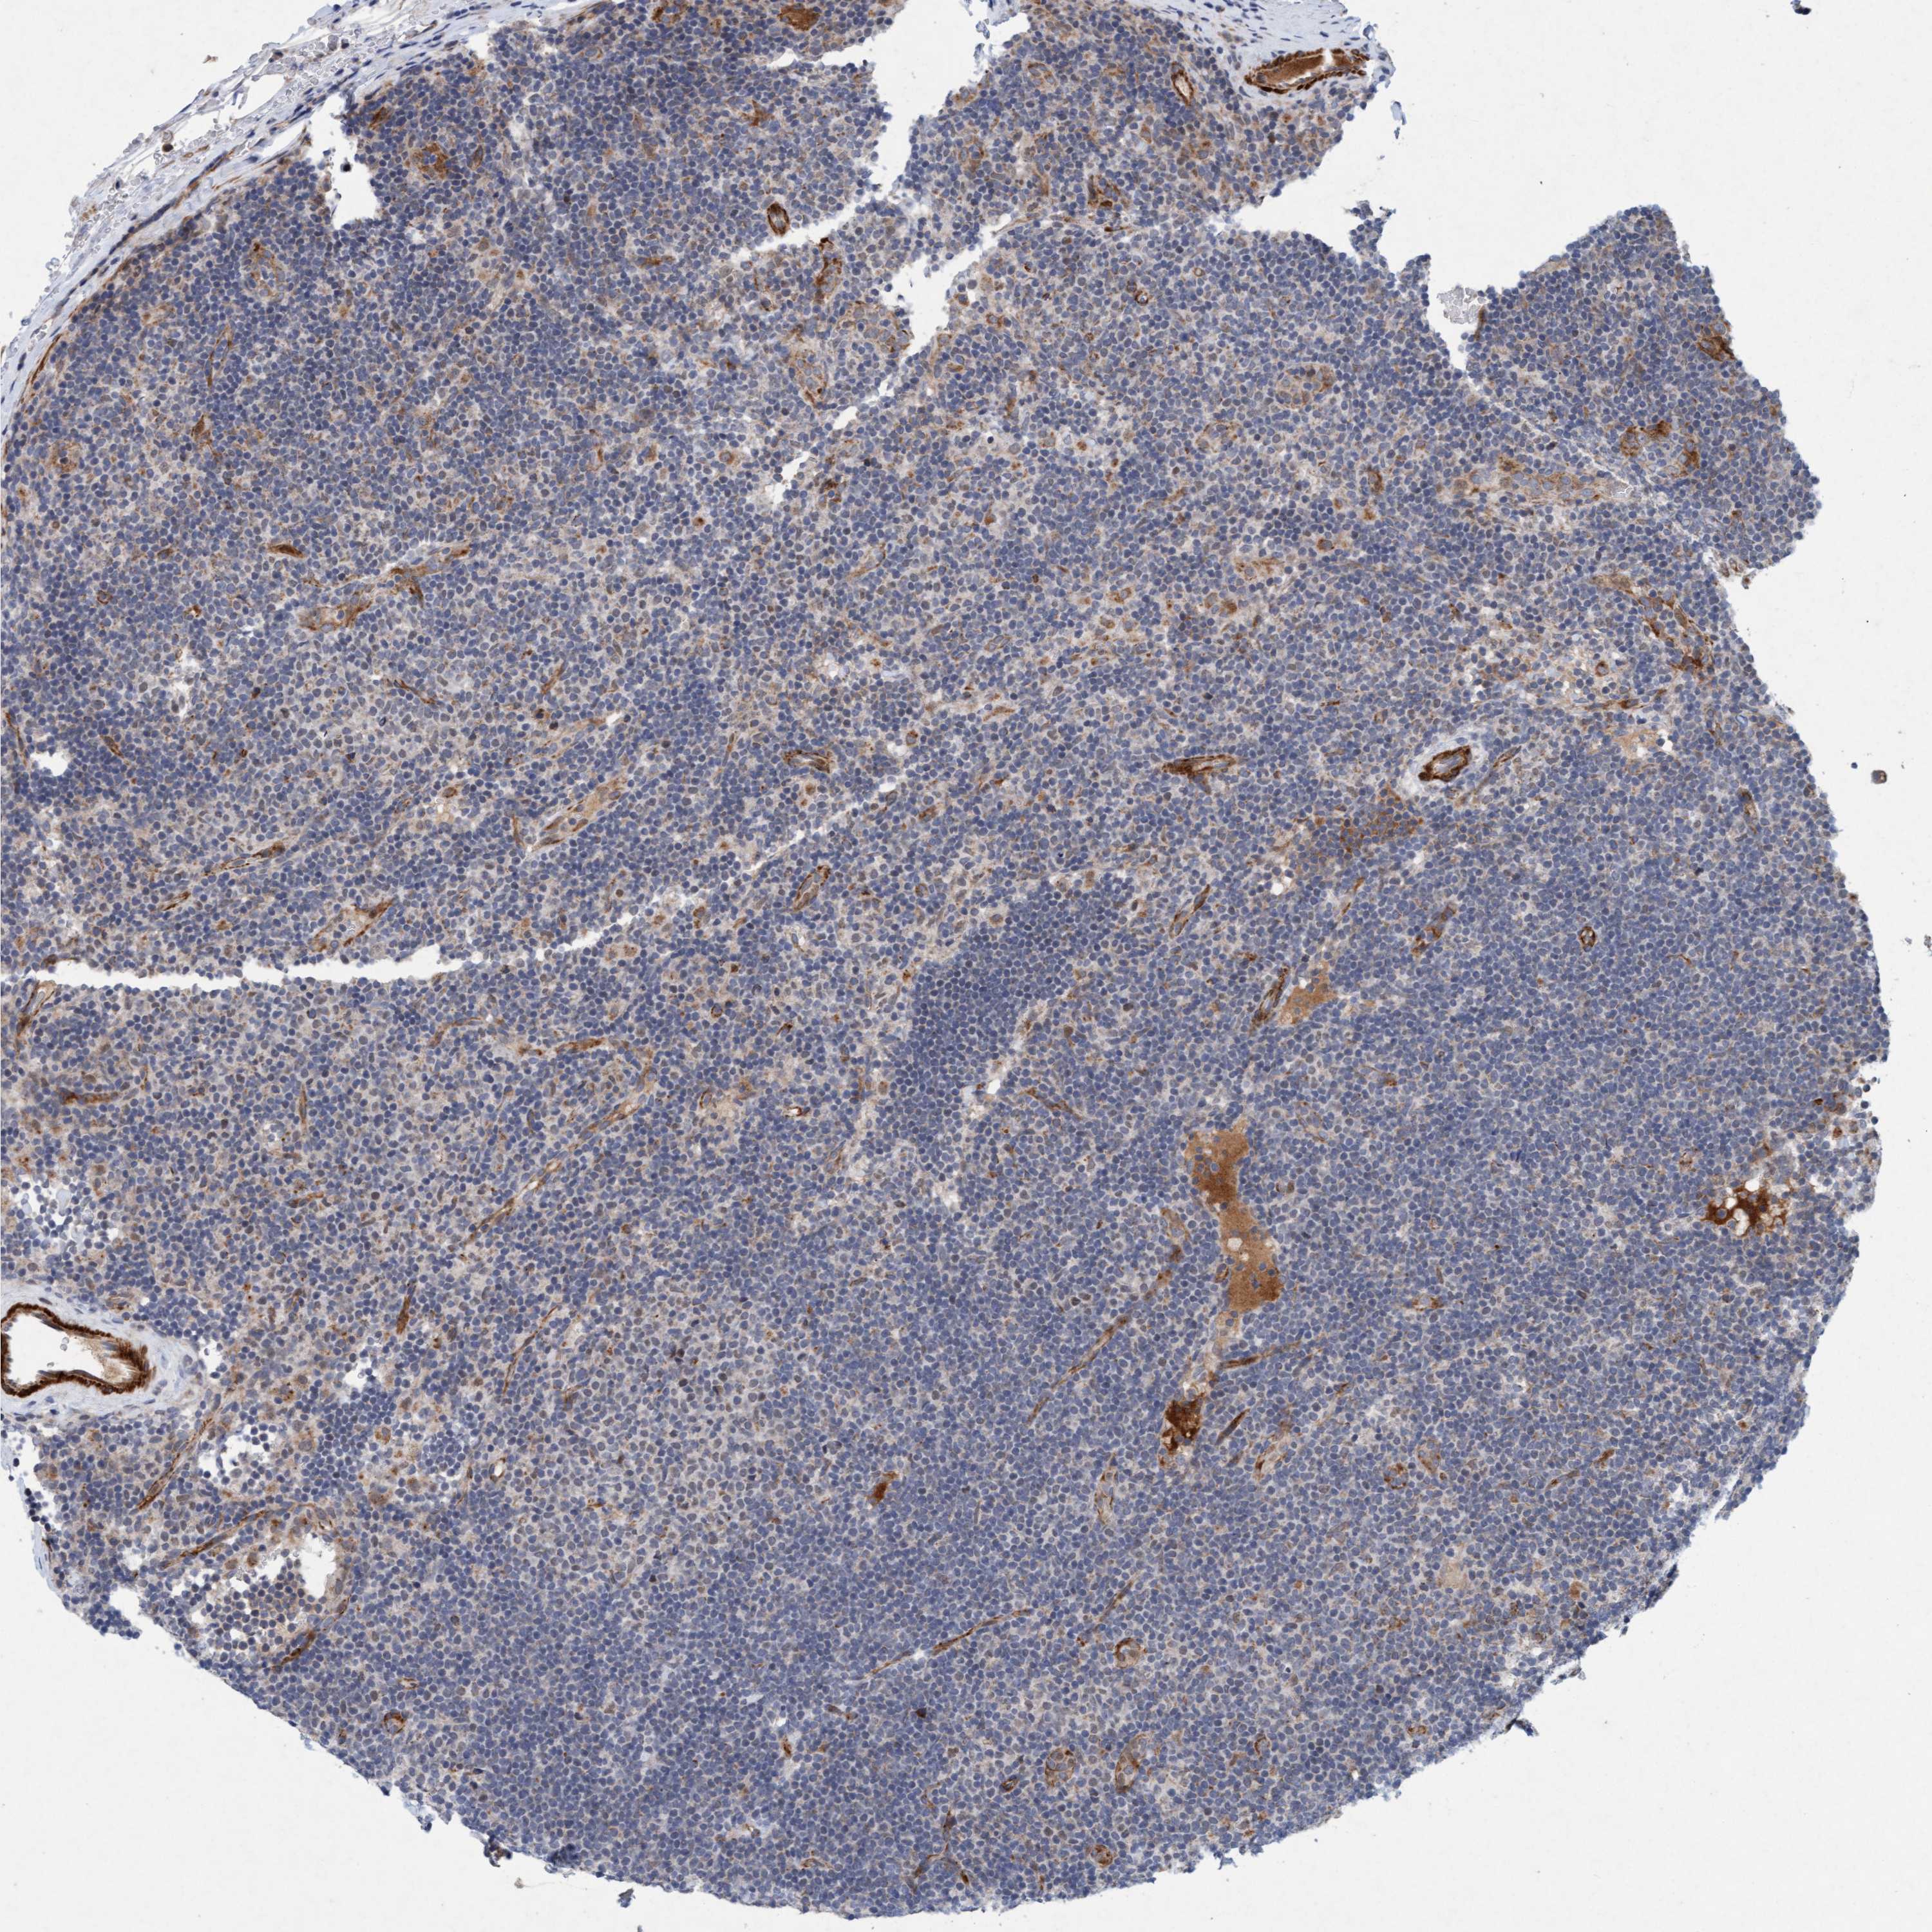

LYMPHOMA - Protein expressioni

A mouse-over function shows sample information and annotation data. Click on an image to view it in a full screen mode. Samples can be filtered based on level of antibody staining by selecting one or several of the following categories: high, medium, low and not detected. The assay and annotation is described here.

Each image is clickable and will lead to virtual microscopy that enables deeper exploration of all samples and also displays staining intensity scores, fraction scores and subcellular localization as well as patient and tissue information for each sample.

Antibody HPA023187

Antibody CAB034226

Staining

High

Medium

Low

Not detected

Intensity

Strong

Moderate

Weak

Negative

Quantity

>75%

75%-25%

<25%

None

Location

Nuclear

Cytoplasmic/membranous

Cytoplasmic/membranous,nuclear

Hodgkin's disease, NOS

Malignant lymphoma, non-Hodgkin's type, High grade

Malignant lymphoma, non-Hodgkin's type, Low grade